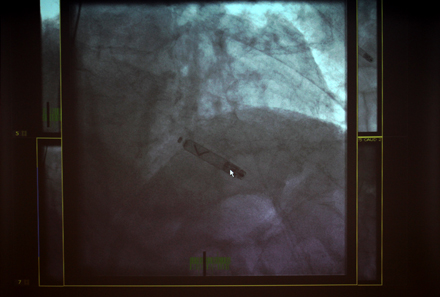

John Ip, M.D., of the Sparrow Clinical Research Institute (SCRI) at Sparrow Hospital has become one of the first physicians in the United States to implant, with great success, a miniature-sized cardiac pacemaker that has no electrical leads directly inside a Patient's heart without surgery.

The new device, made by St. Jude Medical, is being tested in clinical trials at select centers throughout the United States.